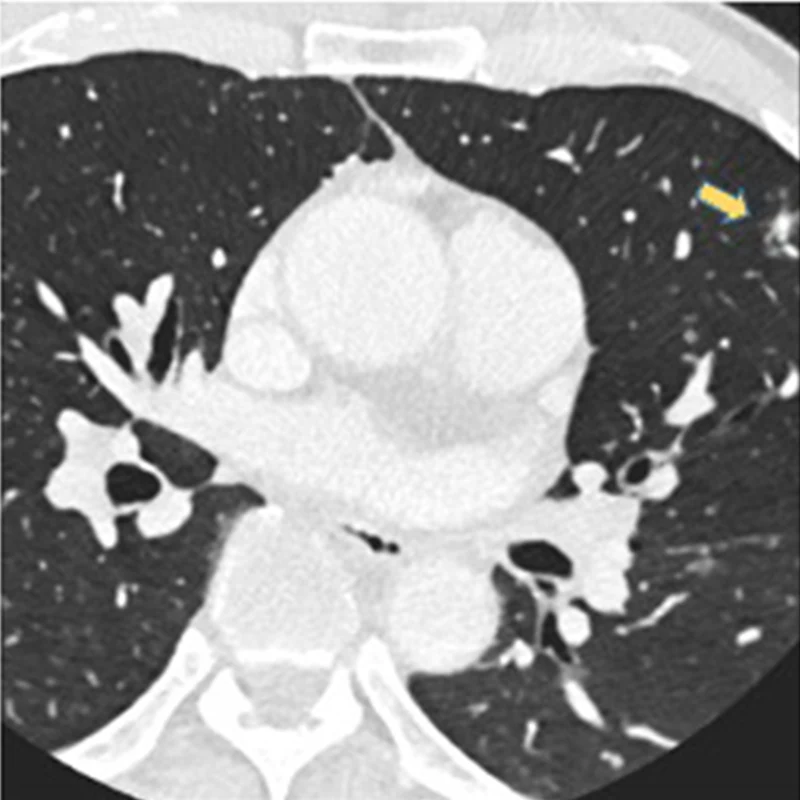

On a coronary angiogram, a nodule is visible in the upper right-hand corner, corresponding to the left upper lobe.

The patient's full chest CT confirmed the nodule in the left upper lobe.